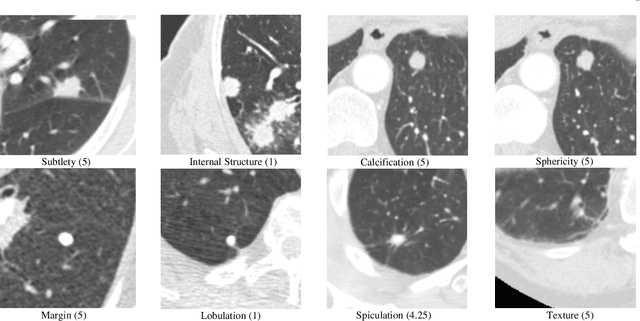

Abstract:During clinical practice, radiologists often use attributes, e.g. morphological and appearance characteristics of a lesion, to aid disease diagnosis. Effectively modeling attributes as well as all relationships involving attributes could boost the generalization ability and verifiability of medical image diagnosis algorithms. In this paper, we introduce a hybrid neuro-probabilistic reasoning algorithm for verifiable attribute-based medical image diagnosis. There are two parallel branches in our hybrid algorithm, a Bayesian network branch performing probabilistic causal relationship reasoning and a graph convolutional network branch performing more generic relational modeling and reasoning using a feature representation. Tight coupling between these two branches is achieved via a cross-network attention mechanism and the fusion of their classification results. We have successfully applied our hybrid reasoning algorithm to two challenging medical image diagnosis tasks. On the LIDC-IDRI benchmark dataset for benign-malignant classification of pulmonary nodules in CT images, our method achieves a new state-of-the-art accuracy of 95.36\% and an AUC of 96.54\%. Our method also achieves a 3.24\% accuracy improvement on an in-house chest X-ray image dataset for tuberculosis diagnosis. Our ablation study indicates that our hybrid algorithm achieves a much better generalization performance than a pure neural network architecture under very limited training data.

Abstract:Refer to the literature of lung nodule classification, many studies adopt Convolutional Neural Networks (CNN) to directly predict the malignancy of lung nodules with original thoracic Computed Tomography (CT) and nodule location. However, these studies cannot tell how the CNN works in terms of predicting the malignancy of the given nodule, e.g., it's hard to conclude that whether the region within the nodule or the contextual information matters according to the output of the CNN. In this paper, we propose an interpretable and multi-task learning CNN -- Joint learning for \textbf{P}ulmonary \textbf{N}odule \textbf{S}egmentation \textbf{A}ttributes and \textbf{M}alignancy \textbf{P}rediction (PN-SAMP). It is able to not only accurately predict the malignancy of lung nodules, but also provide semantic high-level attributes as well as the areas of detected nodules. Moreover, the combination of nodule segmentation, attributes and malignancy prediction is helpful to improve the performance of each single task. In addition, inspired by the fact that radiologists often change window widths and window centers to help to make decision on uncertain nodules, PN-SAMP mixes multiple WW/WC together to gain information for the raw CT input images. To verify the effectiveness of the proposed method, the evaluation is implemented on the public LIDC-IDRI dataset, which is one of the largest dataset for lung nodule malignancy prediction. Experiments indicate that the proposed PN-SAMP achieves significant improvement with respect to lung nodule classification, and promising performance on lung nodule segmentation and attribute learning, compared with the-state-of-the-art methods.